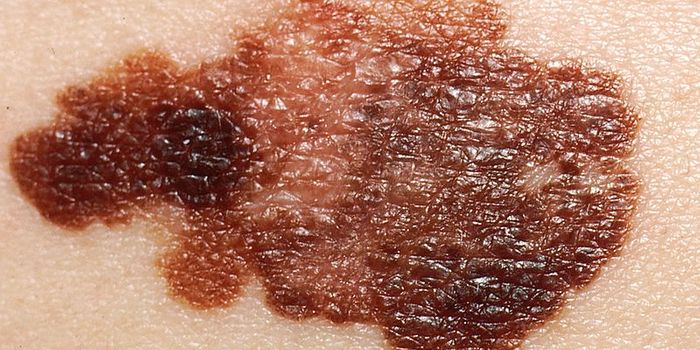

MAR 10, 2021Clinical & Molecular DXMicrobiologists have discovered that the types of bacteria on a dermatitis patient’s skin affect the severity of t ...